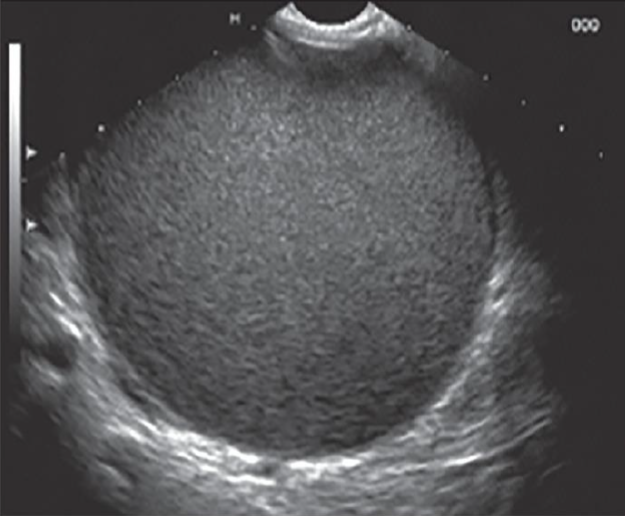

Q

מהו הממצא

A

פסאודו-סיצטה, ציסטה שאינה צלולה

**נראה בד”כ אחרי טראומה או דלקת לבלב